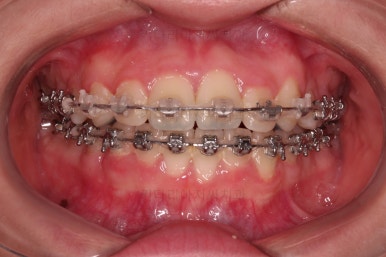

부산교정치료 초진 시 입안의 모습입니다.

치아가 전반적으로 삐뚤고, 덧니가 두드러져 보이네요.

그리고 선을 그려놨는데 윗니의 라인과 아랫니의 라인이 평행이 아니죠.

기울어 있어서 양측의 교합의 강도가 다른 상황이었습니다.

장치를 처음 부착한 사진입니다.

이번 환자분은 특징적으로 윗니의 장치와 아랫니의 장치가 다르죠.

윗니는 좀 더 심미적인 세라믹으로 선택하셨고 아랫니는 비교적 저렴하고 부피가 약간 작고 튼튼한 메탈로 진행했습니다.